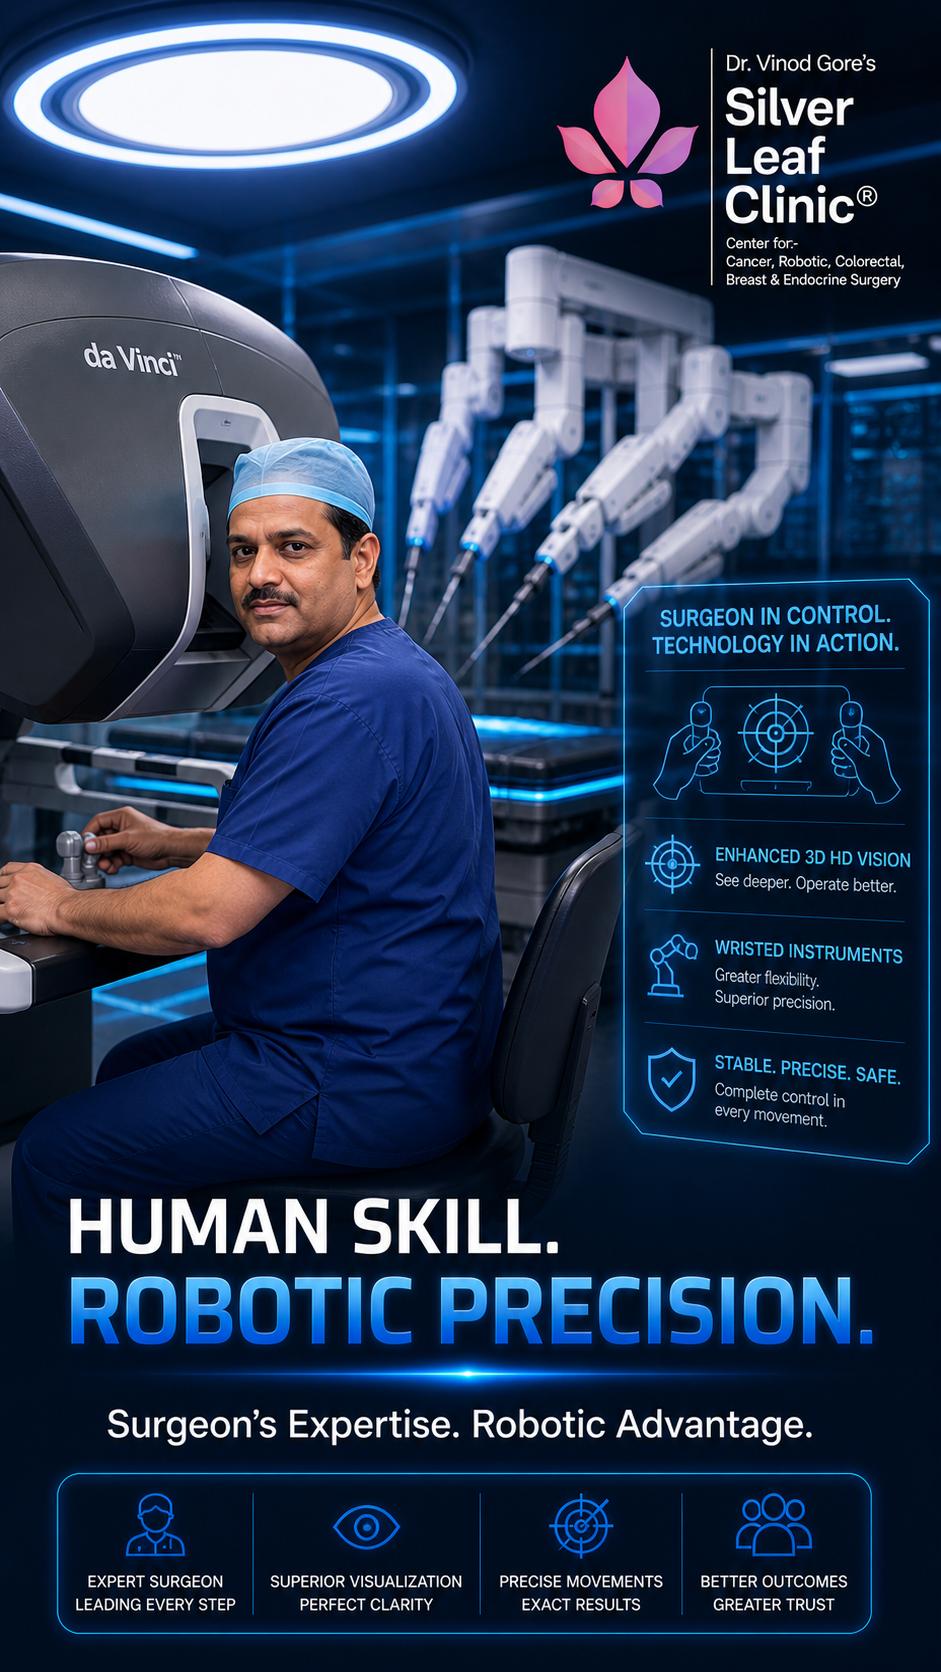

Dr. Vinod T. Gore is a senior surgical oncologist with nearly three decades of experience in advanced cancer surgery, robotic oncosurgery, and complex oncologic procedures. He currently serves as Department Head, Surgical Oncology at Sahyadri Manipal Hospital, Pune — a position he has held since the department's inception in 2009, having played a pioneering role in building its surgical oncology and robotic surgery capabilities from the ground up.

He is internationally trained in advanced robotic surgical techniques, holding the Fellowship in Advanced Robotic and Innovative Surgery (FARIS) from the University of Edinburgh. His robotic programme at Sahyadri Manipal Hospital is a designated Robotic Surgery Centre of Excellence and serves as an accredited FARIS training centre — where Dr. Gore mentors and trains surgical oncology fellows in advanced robotic procedures. These are two distinct and separate recognitions.

Surgeon

Cancer Surgeries

at Tata Memorial

University of

Edinburgh

Center of Excellence in Sahyadri Manipal